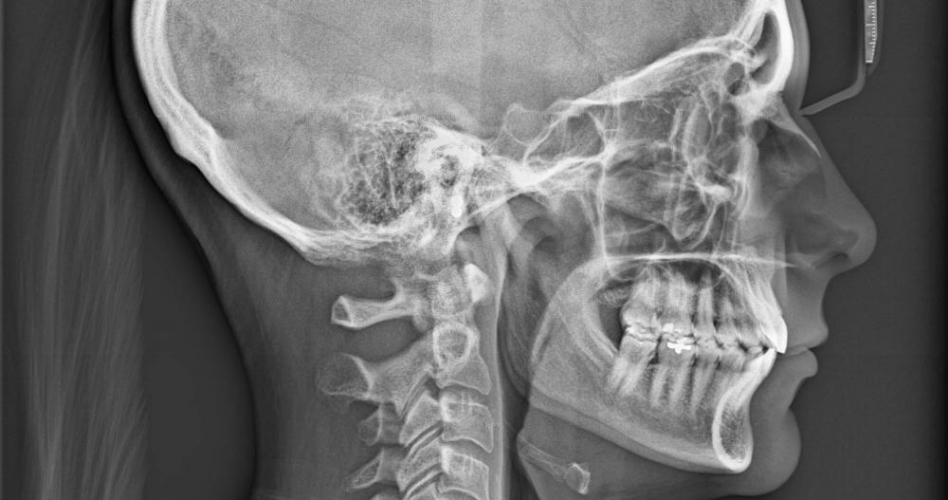

توصل فريق من العلماء الى اكتشاف جديد في جسم الإنسان وتحديدا في منطقة الرأس، حيث تم اكتشاف زوج من الغدد اللعابية الكبيرة، كامنا في الزاوية حيث يلتقي تجويف الأنف مع الحلق.

وتم التوصل لهذا الاكتشاف أثناء فحص مجموعة من صور المسح من آلة يمكنها تصوير الأنسجة بتفاصيل عالية، لاحظ الباحثون وجود جسمين غير مألوفين يقعان في مركز بالرأس، ثنائي من الغدد المسطحة الطويلة بطول بضع بوصات، ملتصق بشكل خفي فوق الأنابيب التي تربط الآذان بالحلق.

وفق تقرير لصحيفة The New York Times الأمريكية، فإن أي كتاب تشريح حديث سيظهر وجود ثلاثة أنواع رئيسية فقط من الغدد اللعابية: أحدها يقع بالقرب من الأذنين، والآخر أسفل الفك، والثالث تحت اللسان، لكن الاكتشاف الجديد يؤكد وجود غدة رابعة.